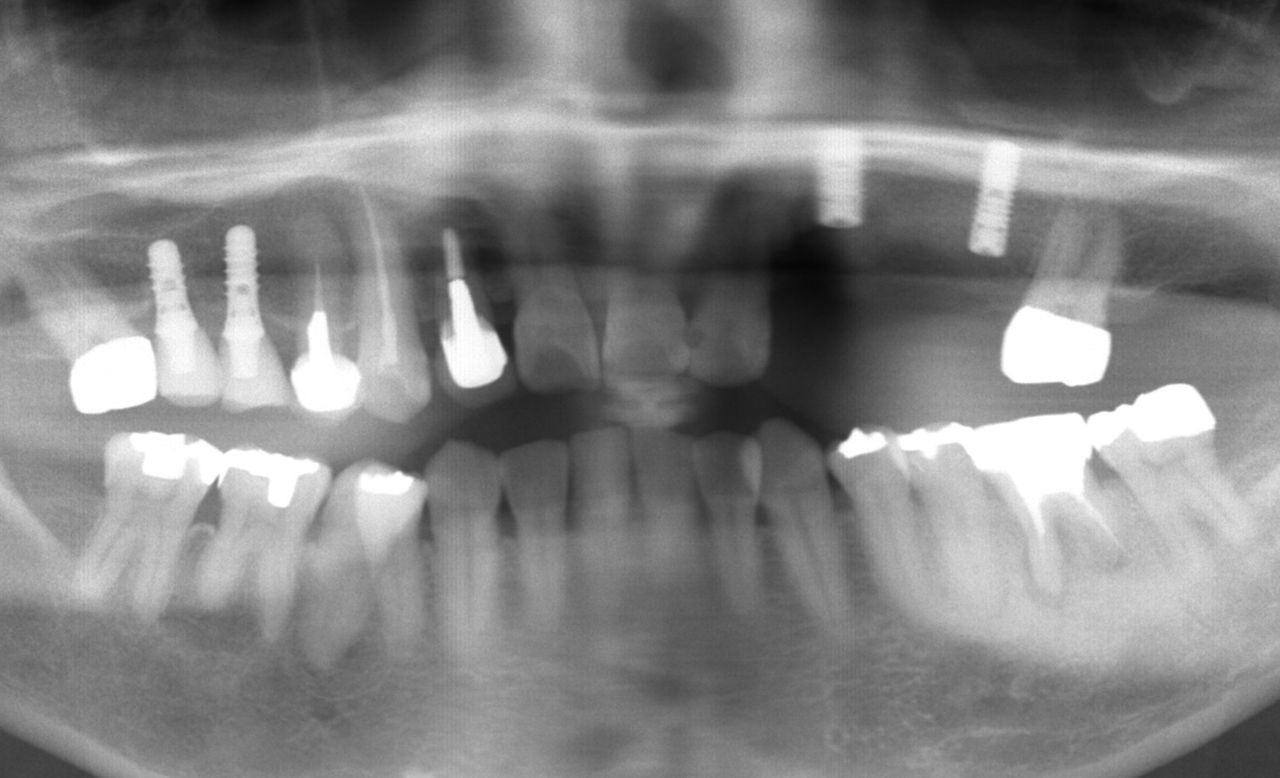

以下が初診時のレントゲンです。

抜歯後、インプラント手術直後が以下のレントゲンです。

下顎左側(皆さんからみて右手側)は、骨が非常に固く

長いインプラントを埋め込むのが困難であったので短いインプラントとなっています。

通常はこうしたことが起こることはほとんどなく、

私の経験の中でも非常に稀なケースと言えます。

使用したインプラントは、

ストローマンの ボーンレベル インプラント です。